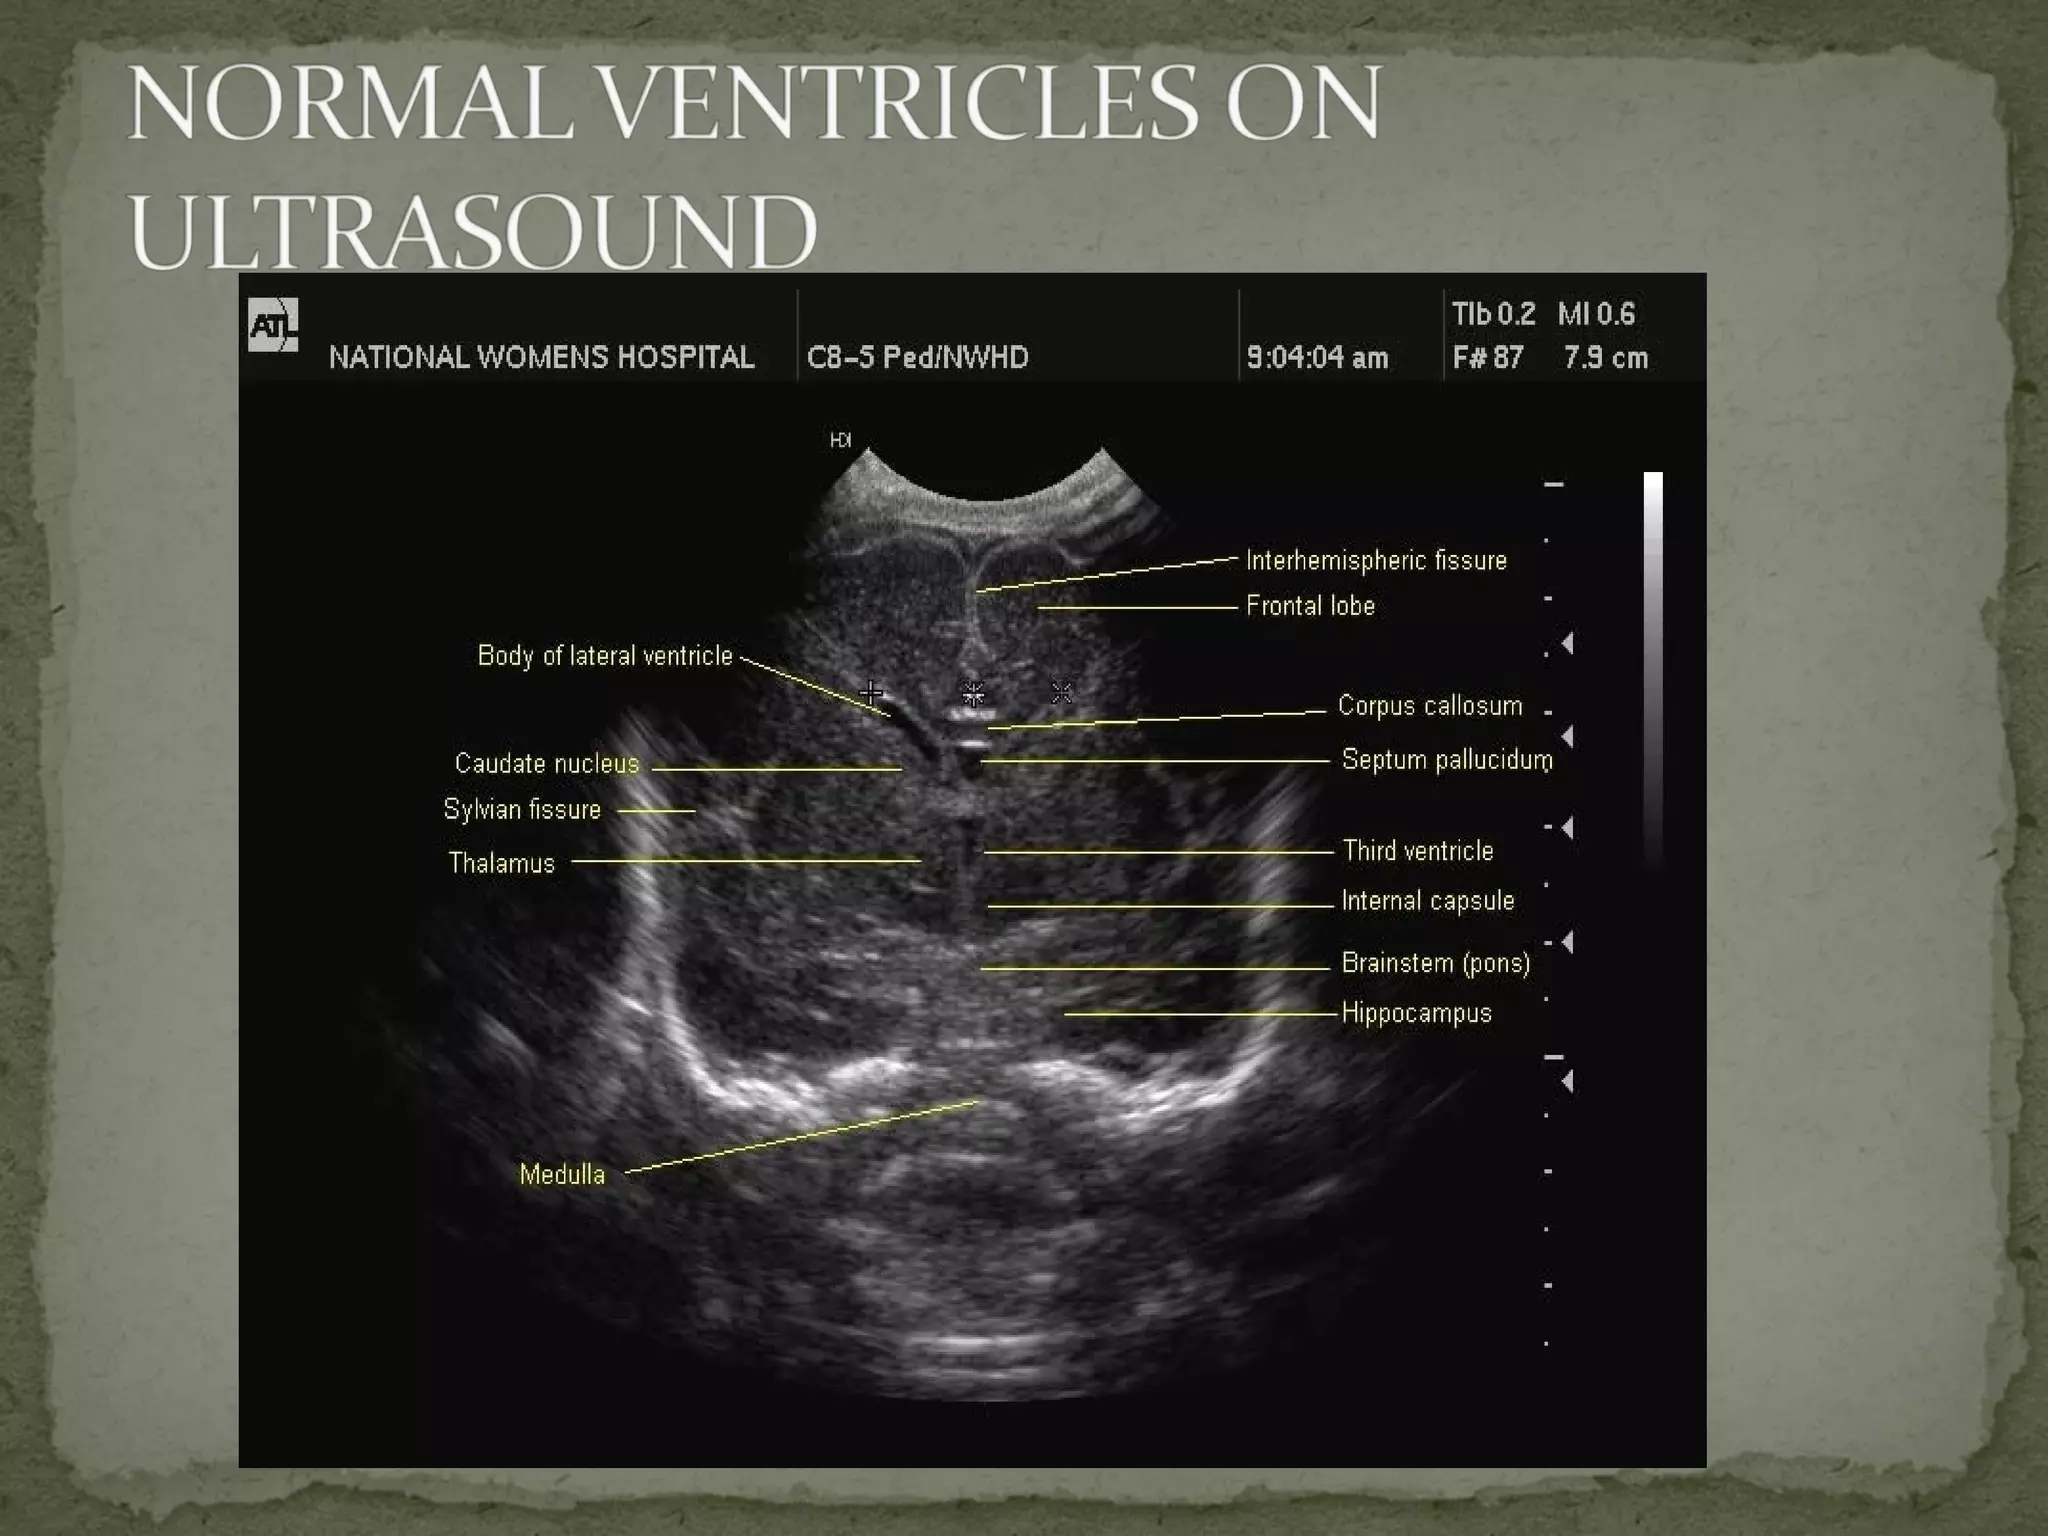

 Ultrasound scan Plain skull X-Ray  CT scan  MRI